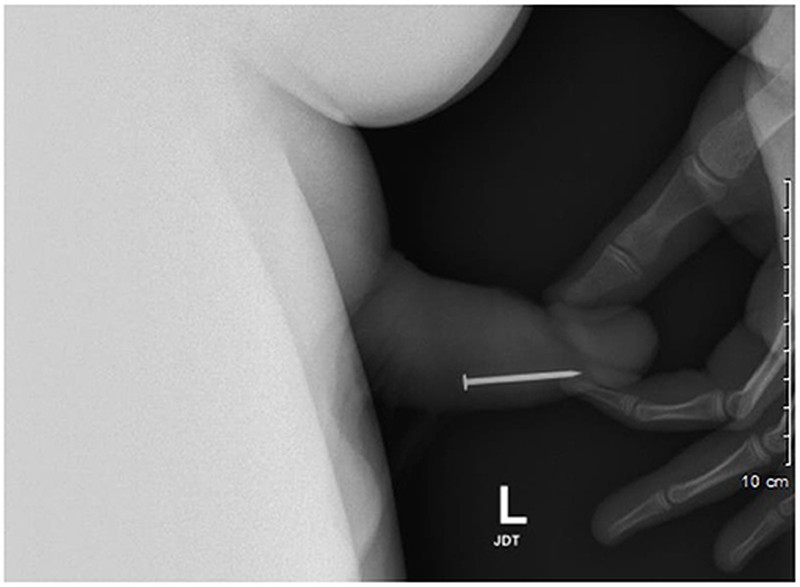

Seorang remaja laki-laki berusia 17 tahun memiliki riwayat memasukkan benda ke dalam uretranya sendiri berkali-kali. Benda yang pertama kali dimasukkan adalah paku, hingga harus dioperasi. (Foto: Adam Bezinque/ jurnal Frontiers In)

Sejak pertemuan pertamanya, ia sudah menjalani total 20 kunjungan ke UGD, dengan 9 di antaranya memerlukan tindakan pengangkatan endoskopi. Dari rontgen panggul, tim medis mengidentifikasi sekrup logam di uretra penis distal. (Foto: Adam Bezinque/ jurnal Frontiers In)